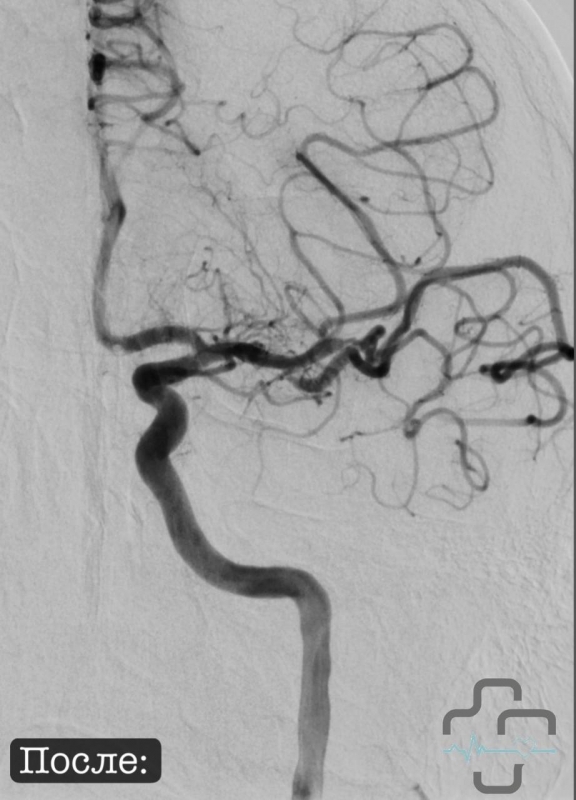

Оперативное вмешательство - внутрисосудистую тромбэктомию в левой средней мозговой артерии - провёл заведующий отделением рентген-хирургических методов диагностики и лечения Александр Владимирович Григорьев. Как отмечают врачи, именно точность и слаженность работы команды помогли сохранить не только жизнь юноши, но и его здоровье.